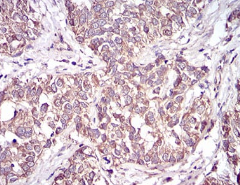

CD36 Mouse Monoclonal antibody[5B6F5]

IHC    1/200 - 1/1000